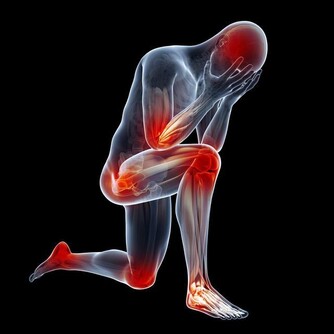

7. 你提前衰老

氧化應激會對整個身體的細胞造成傷害,導致衰老和各種疾病,

所以任何時候你都要保護細胞免受氧化應激的損害。

而硒是一種強大的抗氧化劑,飲食中攝入足夠的硒有助於抗衰老。